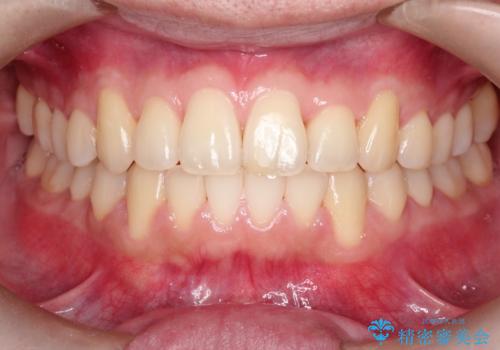

【インビザライン】前歯の凸凹をIPRで改善

- 前歯の凸凹を主訴に来院されました。

前歯を並べるために歯と歯の間にヤスリを入れてわずかに歯を削ることでスペースを確保しています。

歯と歯の間にヤスリを入れてわずかに歯を削ることでスペースを確保する処置をIPRと呼びます。

当院では拡大鏡を用いて丁寧に処置することで歯冠形態を損なわずに行うことができます。